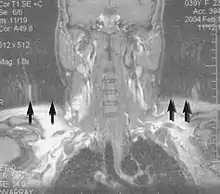

Applications in the musculoskeletal system include spinal imaging, assessment of joint disease, and soft tissue tumors.[42] Also, MRI techniques can be used for diagnostic imaging of systemic muscle diseases including genetic muscle diseases.[43][44]

Swallowing movement of throat and oesophagus can cause motion artifact over the imaged spine. Therefore, a saturation pulse applied over this region the throat and oesophagus can help to avoid this artifact. Motion artifact arising due to pumping of the heart can be reduced by timing the MRI pulse according to heart cycles.[45] Blood vessels flow artifacts can be reduced by applying saturation pulses above and below the region of interest.[46]